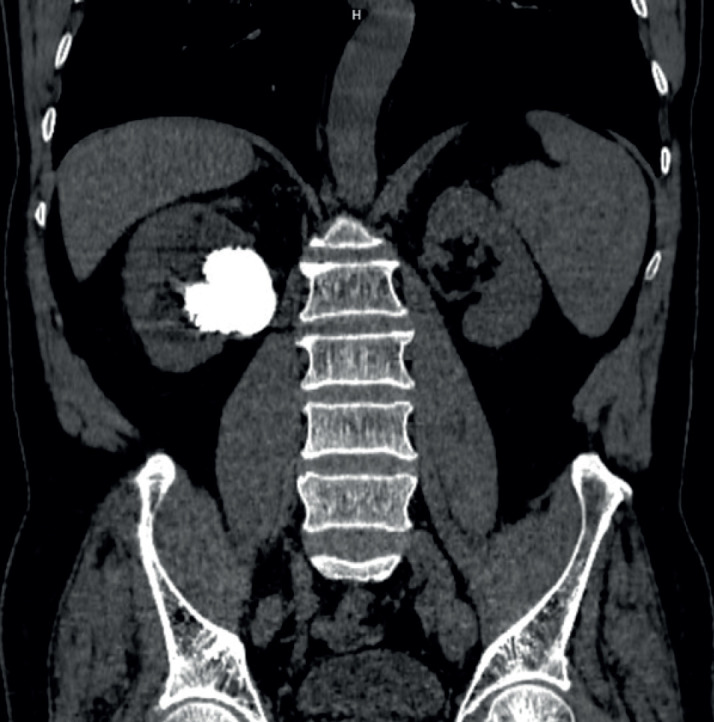

Background: Generally, there are many methods for the treatment of urinary stones, of which percutaneous nephrolithotomy (PCNL) is a minimally invasive and highly effective method, and now become the first-line management for urinary stones, especially in the cases of complex stones and staghorne calculi. Accurate assessment of stone location, stone morphology, degree of hydronephrosis as well as urinary system abnormalities is extremely important in the percutaneous nephrolithotomy strategy.

Methods: Descriptive study on 71 patients with kidney stones, who underwent multi-slice CT scan of the urinary system before PCNL and then PCNL at Hanoi Medical University Hospital from July 2022 to July 2023. All patients received the informed consent and agreed to participate in the study. The factors included the stone area, the track length (from the skin surface to the stone central), the degree of urinary tract dilatation, the number of involved calyces, the density of stone, the renal parenchyma thickness, the ureteral wall thickness and fat infiltration measured on MSCT non-contrast phase. These factors were used to predict the effectiveness of PCNL including the stone clearance rate (SCR) and the operation time.